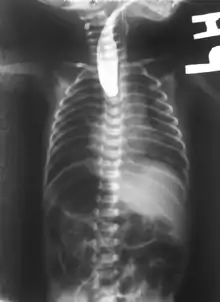

On plain X-ray, a feeding tube will not be seen pass through the esophagus and remain coiled in the upper oesophageal pouch.[3]

If any of the above signs/symptoms are noticed, a catheter is gently passed into the esophagus to check for resistance. If resistance is noted, other studies will be done to confirm the diagnosis. A catheter can be inserted and will show up as white on a regular x-ray film to demonstrate the blind pouch ending. Sometimes a small amount of barium (chalk-like liquid) is placed through the mouth to diagnose the problems.